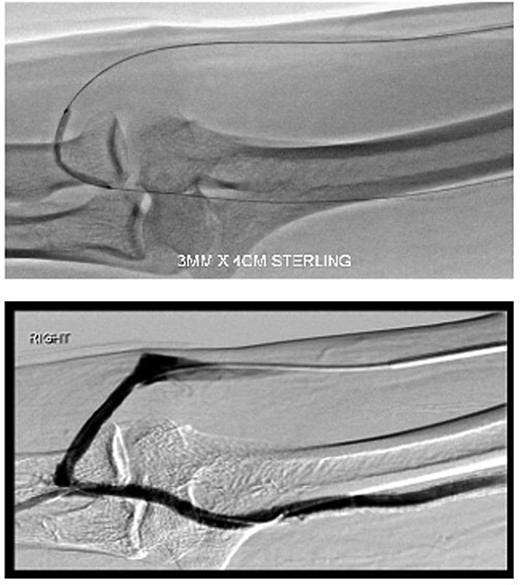

Upon examination 2 days later, the patient’s right hand was significantly colder than his left, with a prolonged capillary refill time of 5 seconds. Pain was alleviated and Doppler signals of his distal arteries were audible only with AVF compression. His digital finger pressure was 36 mmHg, rising to 97 mmHg with fistula compression. A duplex ultrasound revealed patent brachial, ulnar and radial arteries, confirming the diagnosis of DASS (Fig. 3).

Investigations confirming dialysis-associated steal syndrome (DASS).